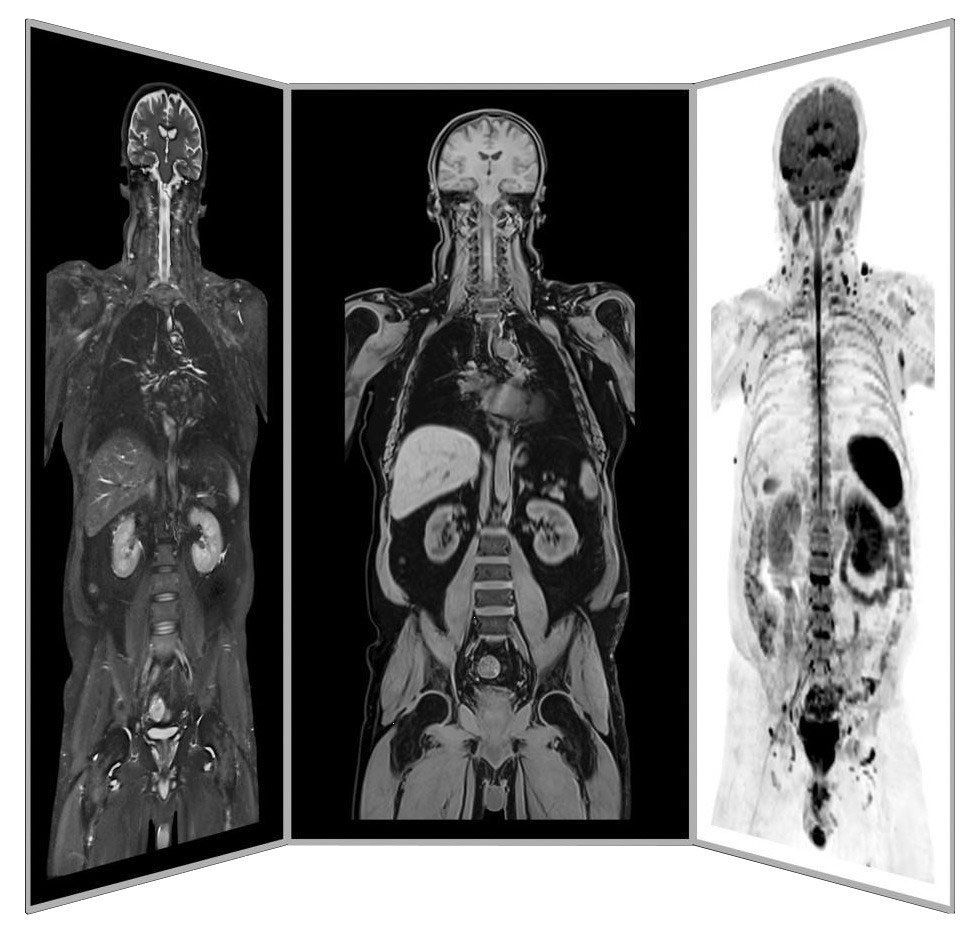

Dr. mult. Michael K. Stehling, der Gründer der ANOVA IRM ist Radiologe und promovierter Physiker. Aus diesem Grund verfügt das ANOVA Institute for Regenerative Medicine in Kooperation mit dem im selben Gebäude befindlichen Prof. Stehling Institut für bildgebende Diagnostik über die Möglichkeit, spezielle Präzisionsdiagnostik wie Arthro-MRT und nicht-radioaktive Kontrastmittel-MRTs anzuwenden.

Im Vergleich zu vielen konventionellen MRTs, sind diese Methoden oft in der Lage, die Schmerz-verursachende Entzündung am oder im Wirbel zu lokalisieren. Hierdurch sind wir in der Lage individuell festzulegen, wie Patienten behandelt werden und wo die Stammzellen angewendet werden sollen.

Darüber hinaus ergänzen wir in Absprache mit Ihnen unsere patientenindividuelle Diagnostik durch spezifische Blutuntersuchungen zu Hormonen, Entzündungsparametern und anderen Faktoren, die in Ihrem Fall wichtig sind oder empfehlen Ihnen weitere Untersuchungen wie z.B. einen präventiven MRT-Wirbelsäulenscan.

Diagnostik-Teil-Körper-MRT

ANOVA IRM © Siemens Healthcare GmbH

Präventive MRT-Untersuchungen sind in vielen Fällen hilfreich. Da keine Strahlenbelastung gegeben ist, können MRTs zur frühzeitigen Diagnose von Arthrose, Arthritis, Sehenenrissen, Bänderrissen und Kapselrissen eingesetzt werden. MRTs sind auch wichtige diagnostische Hilfen bei der Früherkennung von Brustkrebs (Mammakarzinomen) und Prostatakrebs (Prostatakarzinomen). Ganzkörper-MRTs können eingesetzt werden, um eine Früherkennung von Prostatakrebs zu gewährleiten oder Metastasen in Weichgeweben zu lokalisieren. Oft erkennt ein MRT Metastasen früher als ein CT oder eine Röntgenaufnahme.